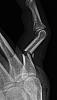

When fighting with the snow blower, keep in mind that said snowblower will try to win at all costs. Also impellers take a second to loose momentum.

Name:	displaced_fracture_2.jpg

Name:	displaced_fracture_1.jpg